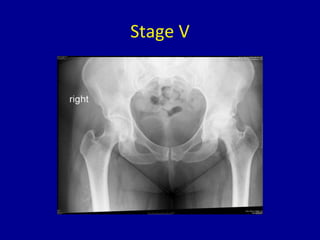

Stage V

• Arthritic changes evident on x-rays with loss of

joint space and spurring

• May affect acetabular side of the joint